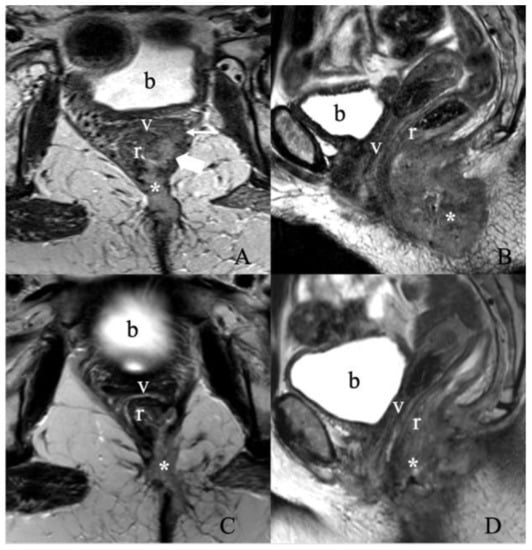

5.2. Stage II

5.3. Stage III

5.4. Stage IV